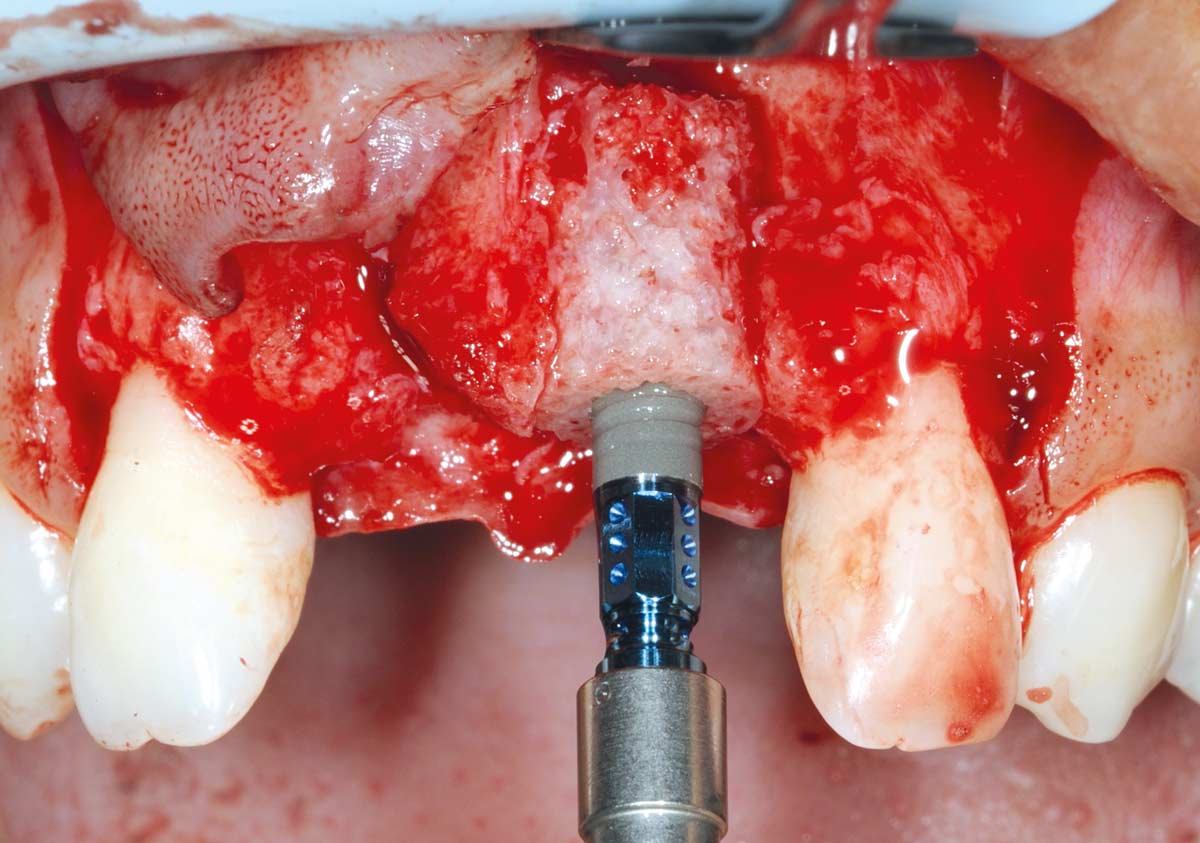

4/26 - Determine the defect size with the trephineBone augmentation in aesthetic zone with maxgraft® bonering - Dr. A. Patel